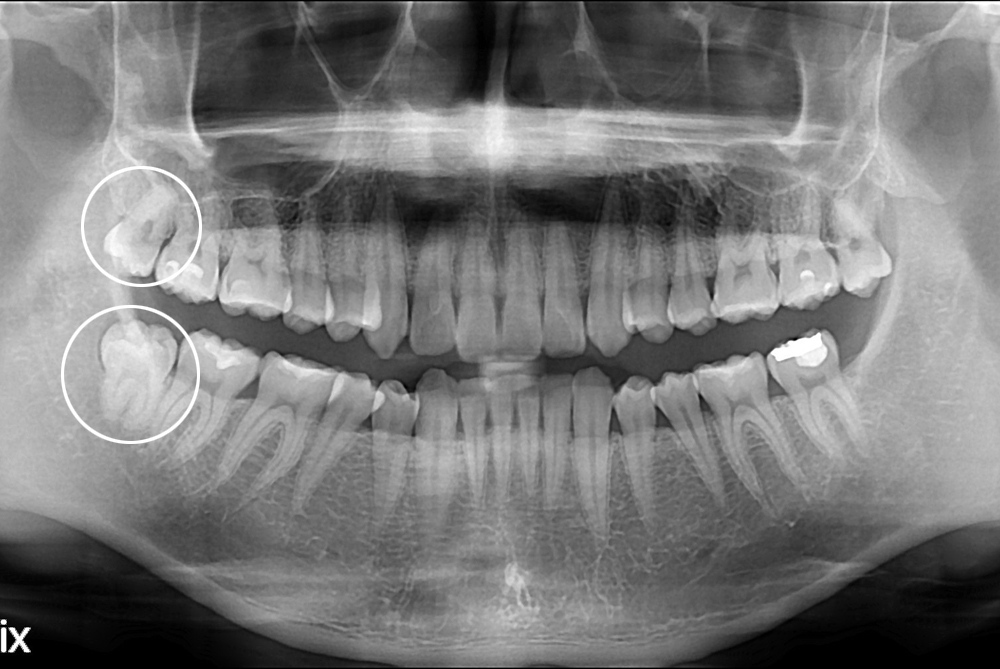

[사랑니] 난발치 사랑니 발치

치료후 : 2017-07-19

세종치과는 구강악안면외과학 박사이신 원장님이 발치하는 치과입니다.